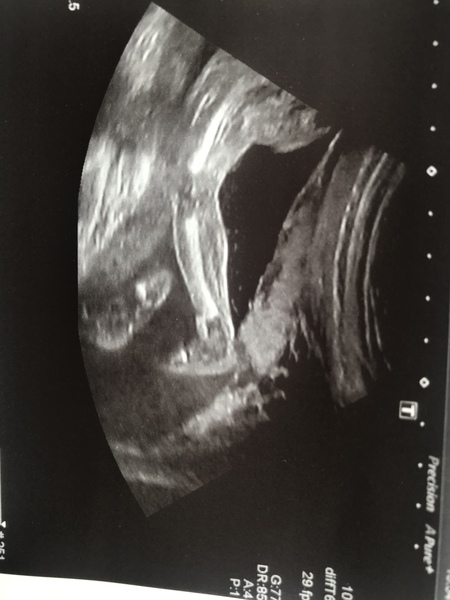

I haven't posted in so long! Not sure If I posted my 20 week scan on the Facebook group but for those that aren't here he is! This was actually a Rescan as he was facing the wrong way at my 20 week so this was on Friday at 22+3!

I can't believe how quickly the pregnancy is going! My two best friends have started to talk about having a baby shower for me! Hope everyone's doing well and I will definitely try and keep up on here as well Smile

20 week gender scan was fine! Baby boy is still a boy haha so thankfully they were right first time! Every scan we have had he has always been on his belly, so have had to try get him to flip over! All body parts are measuring normal and she even said he had his hand wrapped around His willy! 😂 oh put it down to being ‘camera shy’, although I doubt that’s what the ultrasound tech thought! Image is just of his leg! Can’t believe how big he’s grown in 4 weeks

August 2018 #5

@Gem173 glad all is ok! That picture is amazing it's so clear! We had a view from the top of her head where you could see both hands so clearly but unfortunately they didn't take a picture. I think they're much more generous at private scans when you're paying! Doesn't it feel so much more real now? 😍

@Gem173 - congrats on the 20 weeks scan. The leg pic is a good one :)